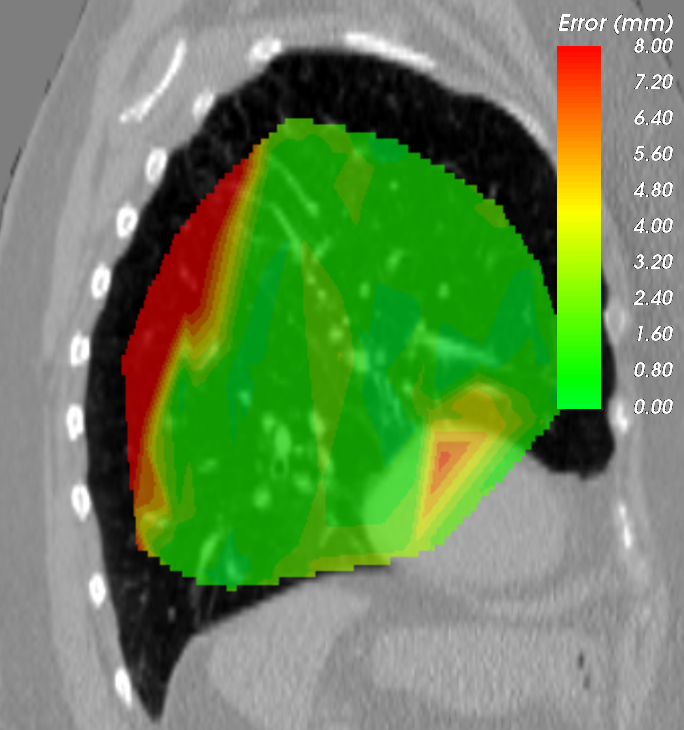

The initial average landmark distance between consecutive phase images was 2.25 1.55 mm for the Popi datasets and 2.19 2.02 mm for the DirLab datasets. The proposed registration algorithm could decrease the average distance to 1.24 0.90 mm and 1.54 1.31 mm, respectively. For a comparison with existing 4D registration methods we applied the publicly available method by [23] to the respiratory datasets and achieved average registration errors similar to the ones of our method: 1.56 1.42 mm for the DirLab and 1.11 0.87 mm for the Popi datasets. The construction of trajectories for voxels requires the combination of all DVF of a 4D dataset. As a consequence the registration error at the start of a trajectory gets propagated over time and increases or decreases with the combination of the different DVF. In Fig. 4 the error evolution is visualised for the three test datasets. At the beginning the mean registration error is 1.54 mm for the DirLab datasets and 1.24 mm for the Popi datasets. The error then increases to a mean of 2.58 mm for DirLab and 2.07 mm for Popi in the middle of the periodic motion. In the end of the breathing cycle the error falls to an error around 1 mm for both datasets. A similar error propagation pattern could be measured for the Sunnybrook datasets. For the Sunnybrook datasets segmentations are only available for the extreme phases, which allows only four comparisons per dataset. When starting with the end-diastolic phase a comparison in the middle of the cyclic motion to the end-systolic segmentation and in the end of the cycle motion to the original end-diastolic segmentation is possible. The same applies when starting with the end-systolic segmentation. In Fig. 4 the red dots indicate the measured DSC overlap, the red dotted line was fitted to the dots and estimates the DSC overlap for phase images without a segmentation available. Compared to a direct registration of the maximum exhale and inhale phases the registration error increased on average by 0.48 mm with the combination of the DVF. The average registration error for the extreme phases in the Popi dataset increased from 1.46 1.59 mm to 1.98 1.56 mm when we registered the whole 4D dataset instead of the two extreme phases solely. The same analysis reported an increase from 1.83 2.35 mm to 2.54 2.01 mm for the DirLab images and and decrease in the DSC from 0.86 0.10 to 0.79 0.14 for the Sunnybrook data. The DVF of the 4D evaluation showed a FoF of 0.02 % and an average Jacobi determinant of 1.00 0.06.

a) DirLab08 deformation grid

for inhale to exhale registration

a) DirLab08 deformation grid

for inhale to exhale registration

b) DirLab08 with overlayed image foldings

(Jacobi determinant 0)

b) DirLab08 with overlayed image foldings

(Jacobi determinant 0)

c) DirLab08 registration error

c) DirLab08 registration error